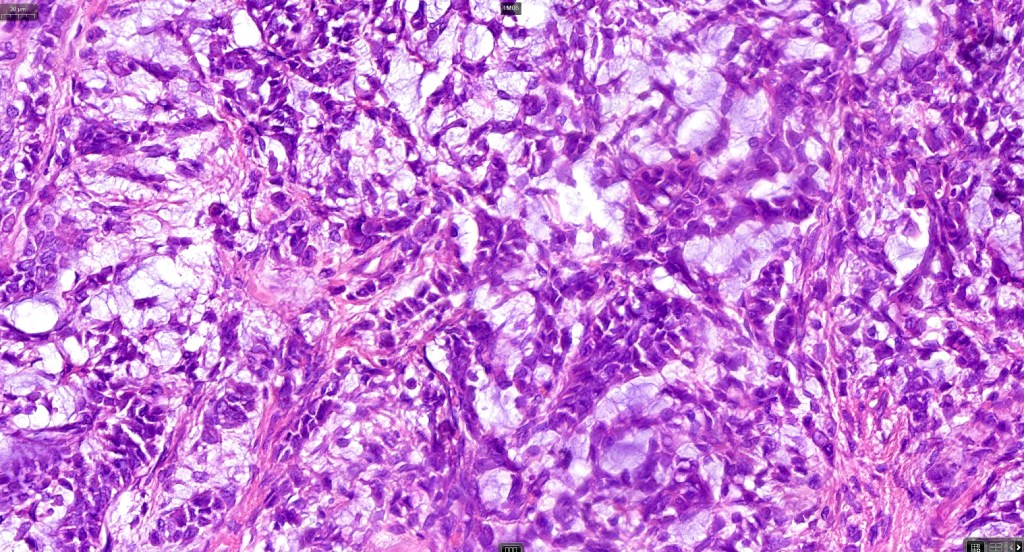

Histological features

•Pure population of myoepithelial cells dispersed in sheet-like, reticular, whorled or fascicular patterns in a myxoid or hyaline stroma

•Cell types include epithelioid, spindled, histiocytoid & plasmacytoid

•Oncocytic & clear cell sometimes present

•No glandular or ductal differentiation

•In malignant myoepithelioma there is an infiltrating border, marked pleomorphism, high mitotic rate & necrosis. Perineural infiltration & lymphovascular invasion may be seen